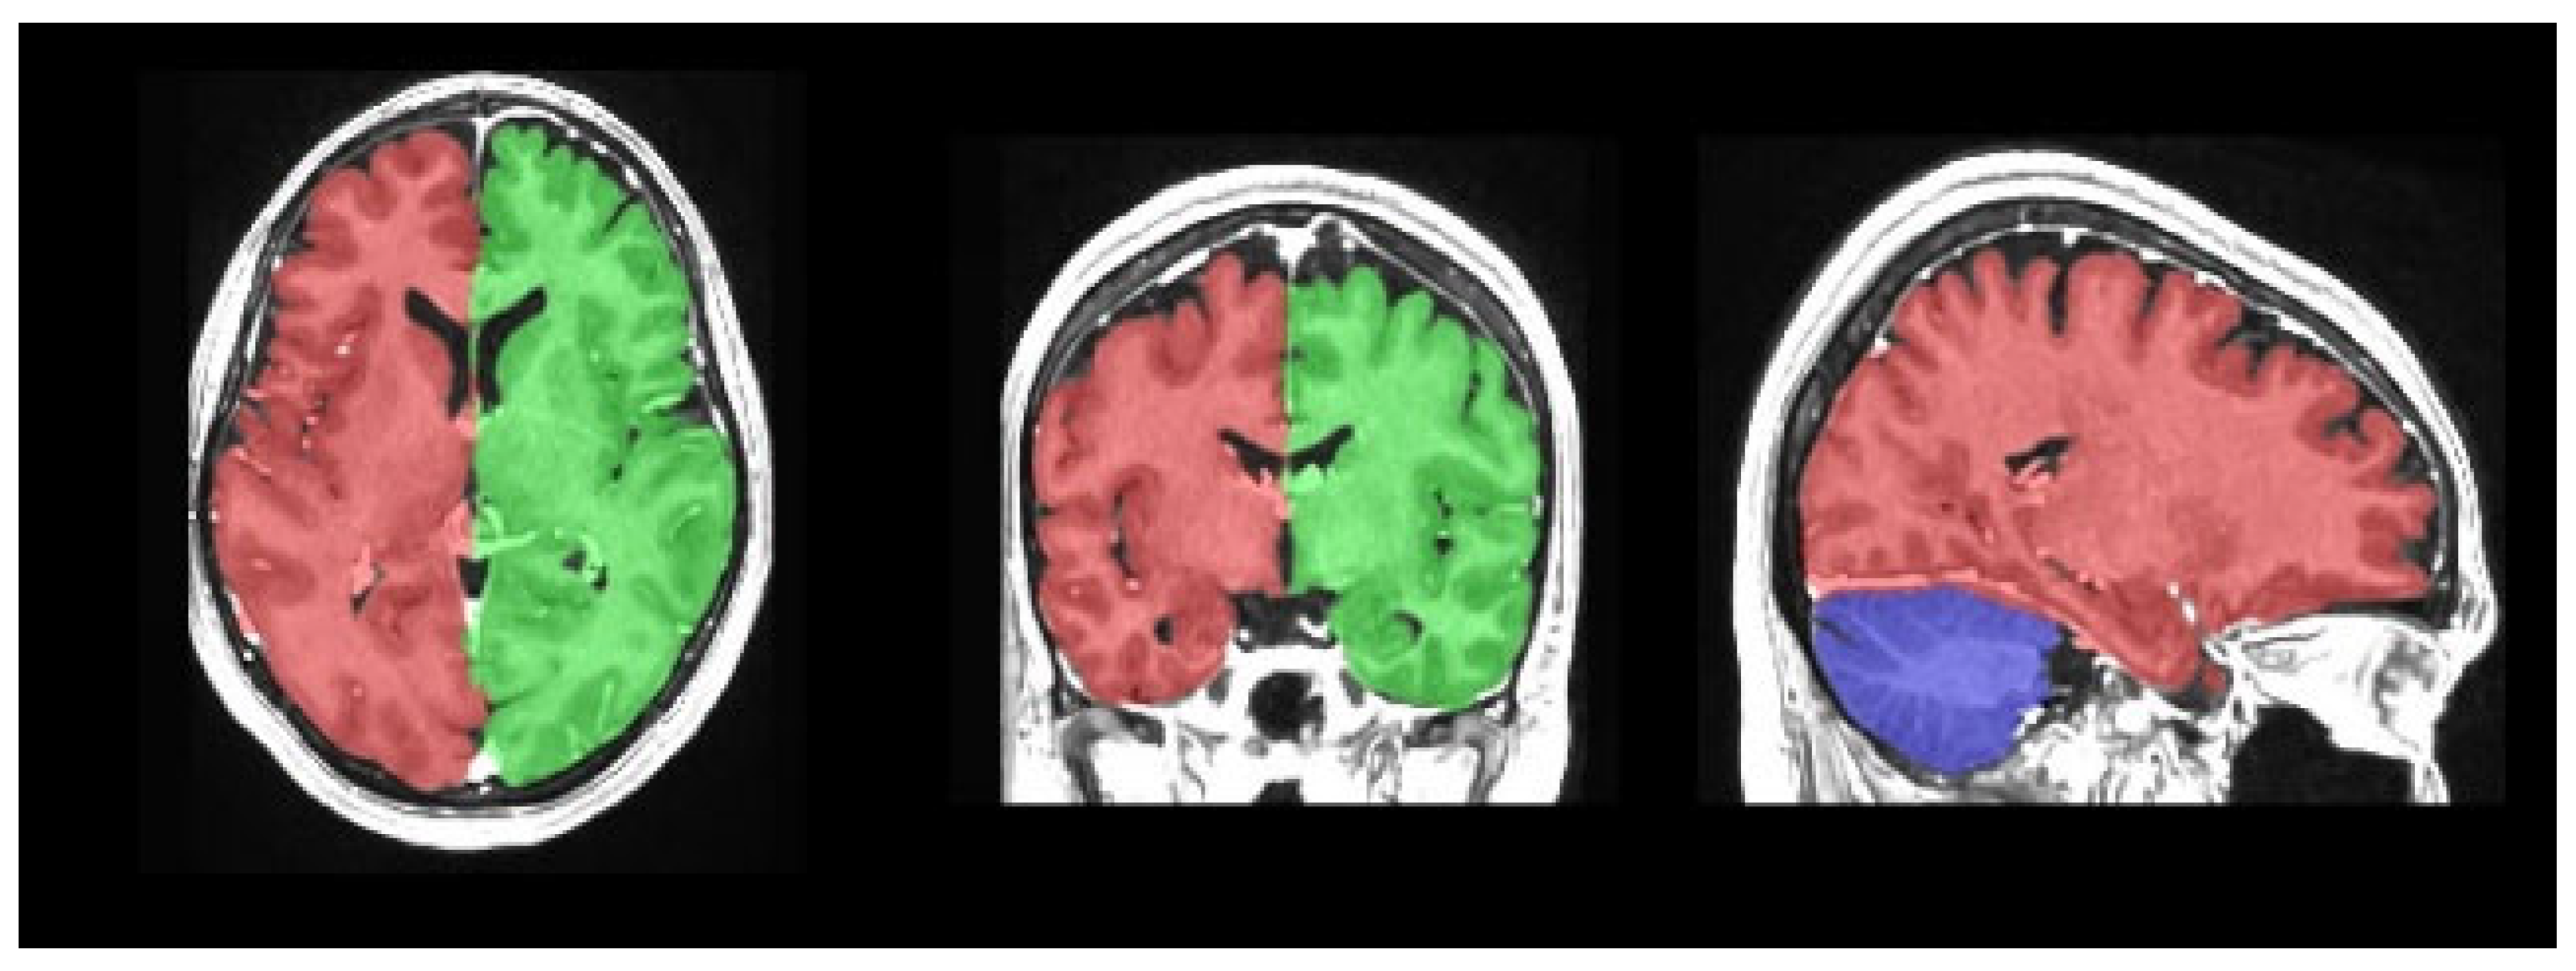

- Manjón, J.V.; Coupé, P. volBrain: An Online MRI Brain Volumetry System. Front. Neuroinform. 2016, 10, 30. [Google Scholar] [CrossRef]